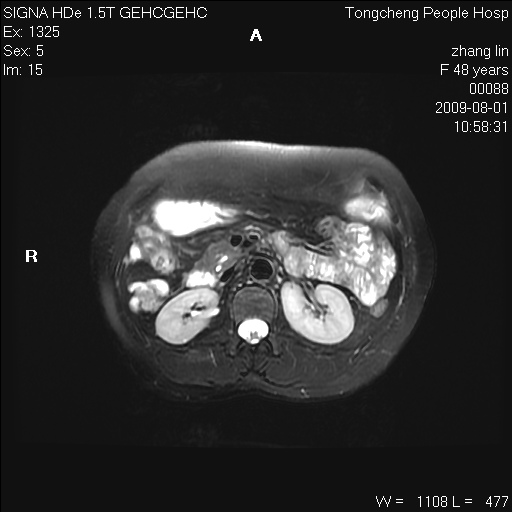

女,48岁。健康体检,彩超发现右肾占位性病变。平素健康。

临床诊断:右肾占位性病变,性质待定(囊肿?肿瘤?)。

上中腹部mr平扫+增强扫描,图像如下:

右肾上极见一类圆形病灶,t1wi呈等信号t2wi呈等高混杂信号,三期增强无强化,边界清---考虑囊肿出血。

同反相位均表现为等信号,病变无强化,考虑含蛋白的囊肿可能,弥散加权相或许有些帮助,